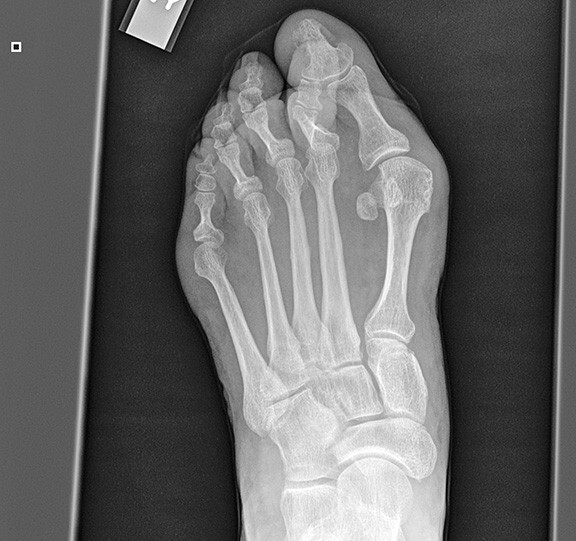

Hallux Abducto Valgus (Bunion Deformity)

Hallux valgus is one of the most recognizable deformities of the foot. (See Figures 3-7.) Investigators consistently have reported that this disorder is more common in females than males; however, this finding may be inaccurate, since the studies cited were based on relatively small numbers of subjects.22 Women are more likely than men to consult with their primary care physicians. The true prevalence of hallux valgus in the general population remains unknown. Many factors, including foot type, biomechanical instability, shoe gear, and other hereditary factors, affect the development of this deformity. Women generally have more issues with foot gear, thus giving the appearance that symptomatic hallux valgus deformity occurs more in women. 23

Figure 4. X-Ray of a Bunion

Hallux valgus is a progressive subluxation of the first metatarsal phalangeal joint. The normal anatomic variant is slight lateral deviation in the great toe with a hallux valgus angle of less than 15 degrees. Mild deformities exhibit an angle of 20 degrees, with moderate deformities at 30 degrees and severe deformities more than 40 degrees. As the hallux moves laterally, retrograde force is placed proximally on the first metatarsal head. The medial and dorsal medial aspect of the first metatarsal becomes “prominent,” thus leading to the bunion formation. Over time, uneven degeneration of the first metatarsal phalangeal joint can lead to arthritis. It is important for the clinician to be able to differentiate the etiology of patient’s symptoms.

The presenting symptoms include pain in the medial aspect of the metatarsal phalangeal joint, with redness and swelling at the area of excessive shoe pressure. There may or may not be pain with range of motion of the metatarsal phalangeal joint. The range of motion can be mildly decreased.

Initial treatment depends on the severity of the deformity. In mild cases, wider or larger shoes will give adequate relief. If there is a concomitant bursitis of the joint, nonsteroidal anti-inflammatory medications may be of great benefit in the short term. Various types of padding may be used to cushion the medial joint space. Foot orthoses can support and offload the first metatarsal phalangeal joint to take weight off the area. Some patients may present with increased pain with a mild or moderate deformity, which can be explained by an entrapment of the medial saphenous nerve.

Surgery can be beneficial in hallux valgus deformities that are painful and in the moderate to severe range. There are many surgical procedures described in the literature, but the goal is to reduce the hallux valgus angle and to relocate the first metatarsal phalangeal joint to a more anatomic position. Surgeries include soft tissue balancing of the first metatarsal phalangeal joint combined with osteotomies of the great toe and first metatarsal to realign the toe. Sometimes, an arthrodesis of the first metatarsal tarsal joint is required to address any instability of that joint to stabilize and reduce the first intermetatarsal angle to an anatomic position.